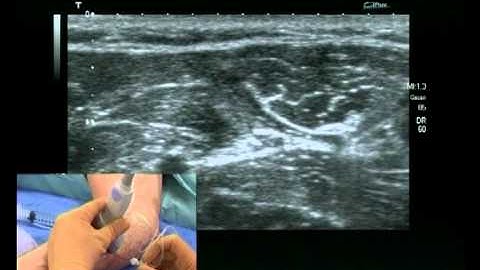

How to Hydrodissect and Block the Ulnar Nerve Using Ultrasound-Guidance